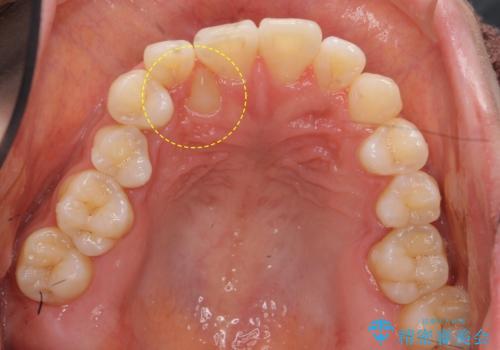

右上の犬歯が内側に生えていました。

右上の半分埋まっている犬歯を抜歯し、残り上下左右3本抜歯してワイヤー矯正を行いました。

犬歯の抜歯後は骨が少ない状態なのでブラックトライアングルは出てしまいましたが事前に説明をしております。